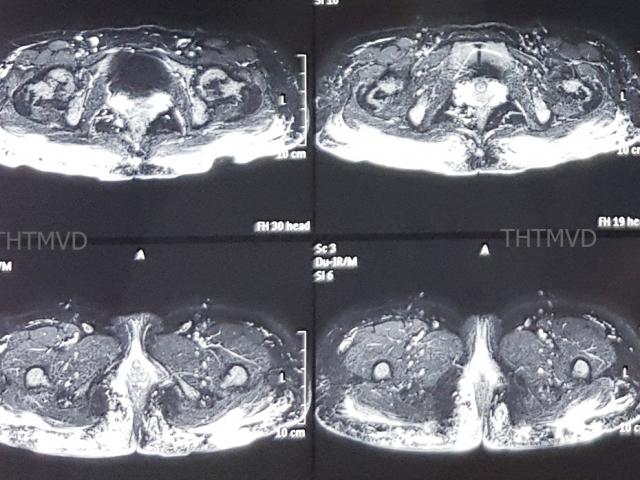

Vào một ngày, ông Lâm và hàng xóm cãi nhau, đột nhiên ông bị đau đầu dữ dội rồi ngã quỵ xuống đất. Hàng xóm thấy vậy hốt hoảng gọi xe cứu thương đưa đến bệnh viện. Sau khi kiểm tra, bác sĩ phát hiện bệnh nhân bị xuất huyết não, dù đã cấp cứu tận tình nhưng không qua khỏi.

Ảnh minh họa.